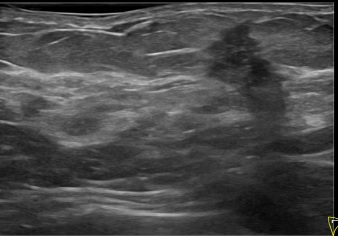

상기환자는 만져지는 멍울로 내원하신 60대초반

여성분으로 의심스러운 좌측혹 조직검사 시행해 유방암 진단되었습니다